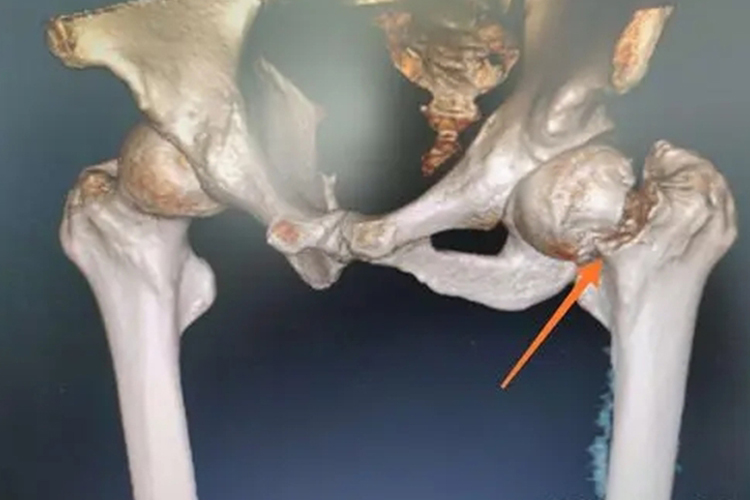

股骨颈骨折

股骨颈骨折是髋关节股骨头与股骨基底连接的位置发生骨折,按骨折线部位分类,可分为股骨头下骨折、股骨颈基底骨折、经股骨颈骨折。